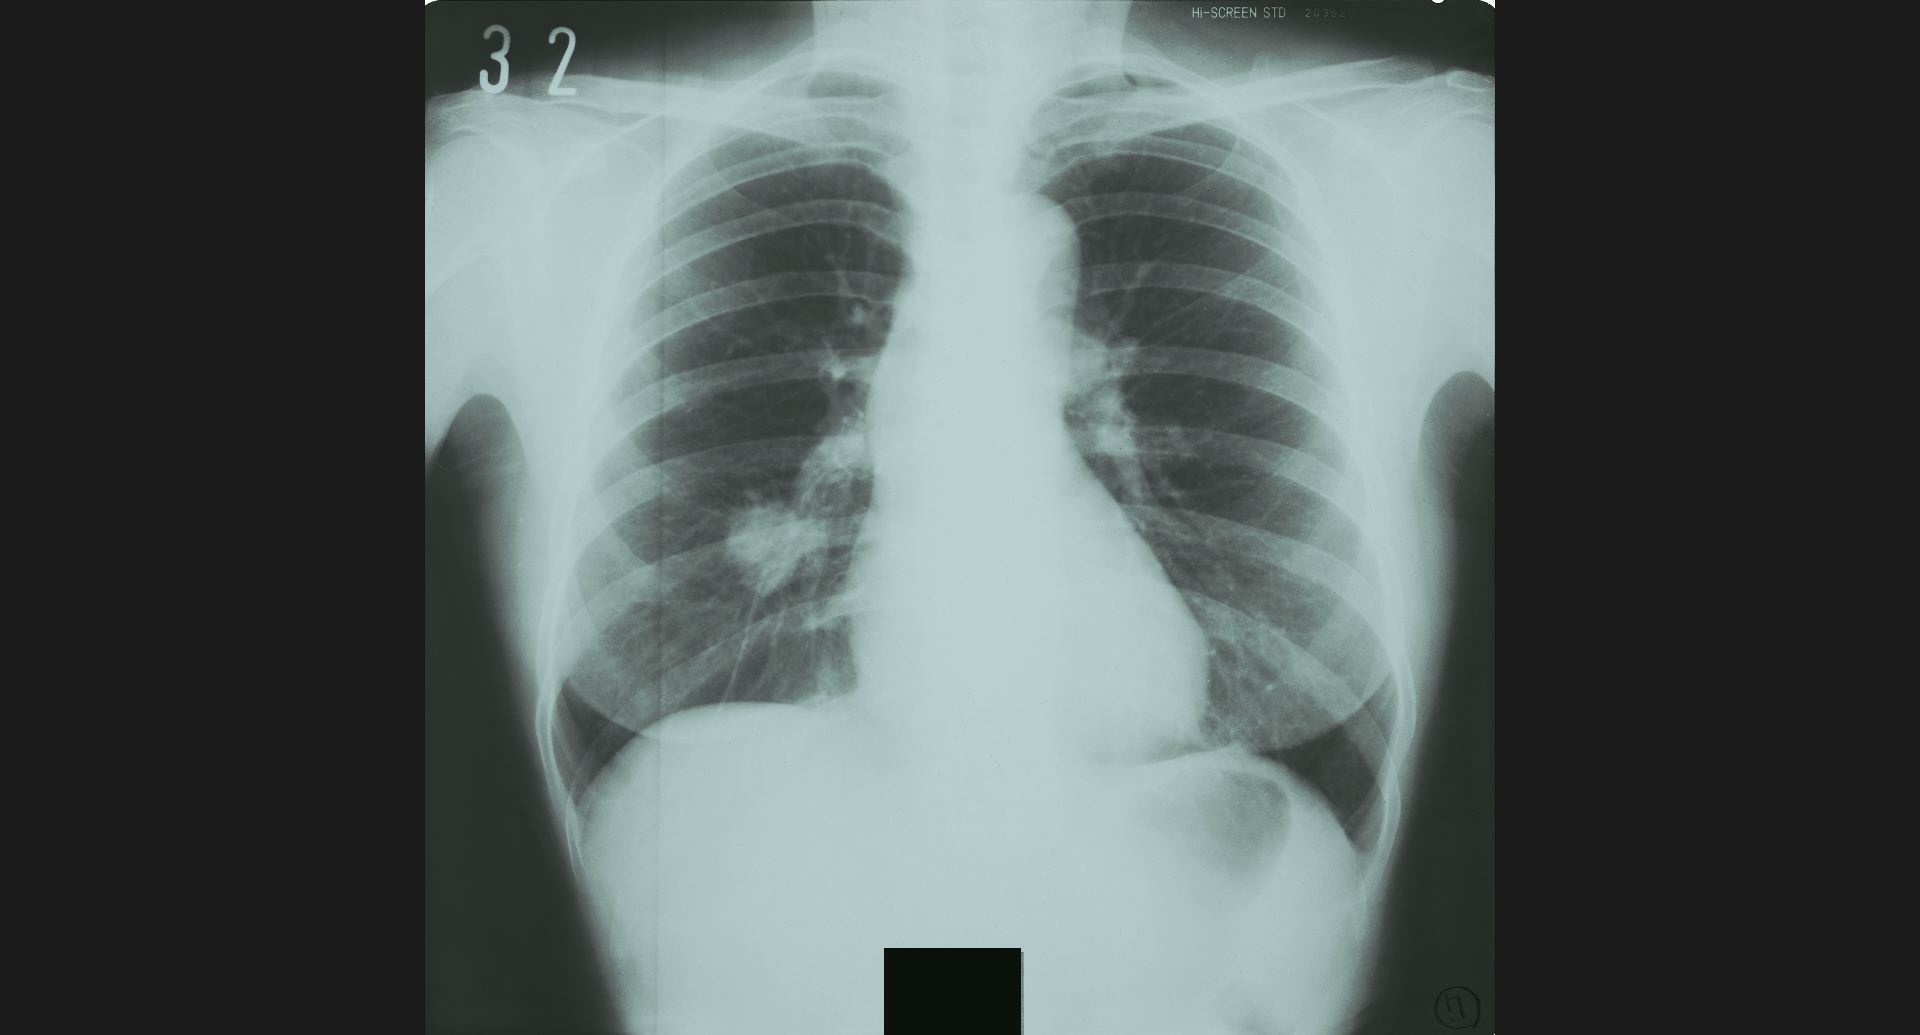

fig.5(93KB)

:Post-plomboge chestピンポン玉、左肺上葉の細かい石灰巣。